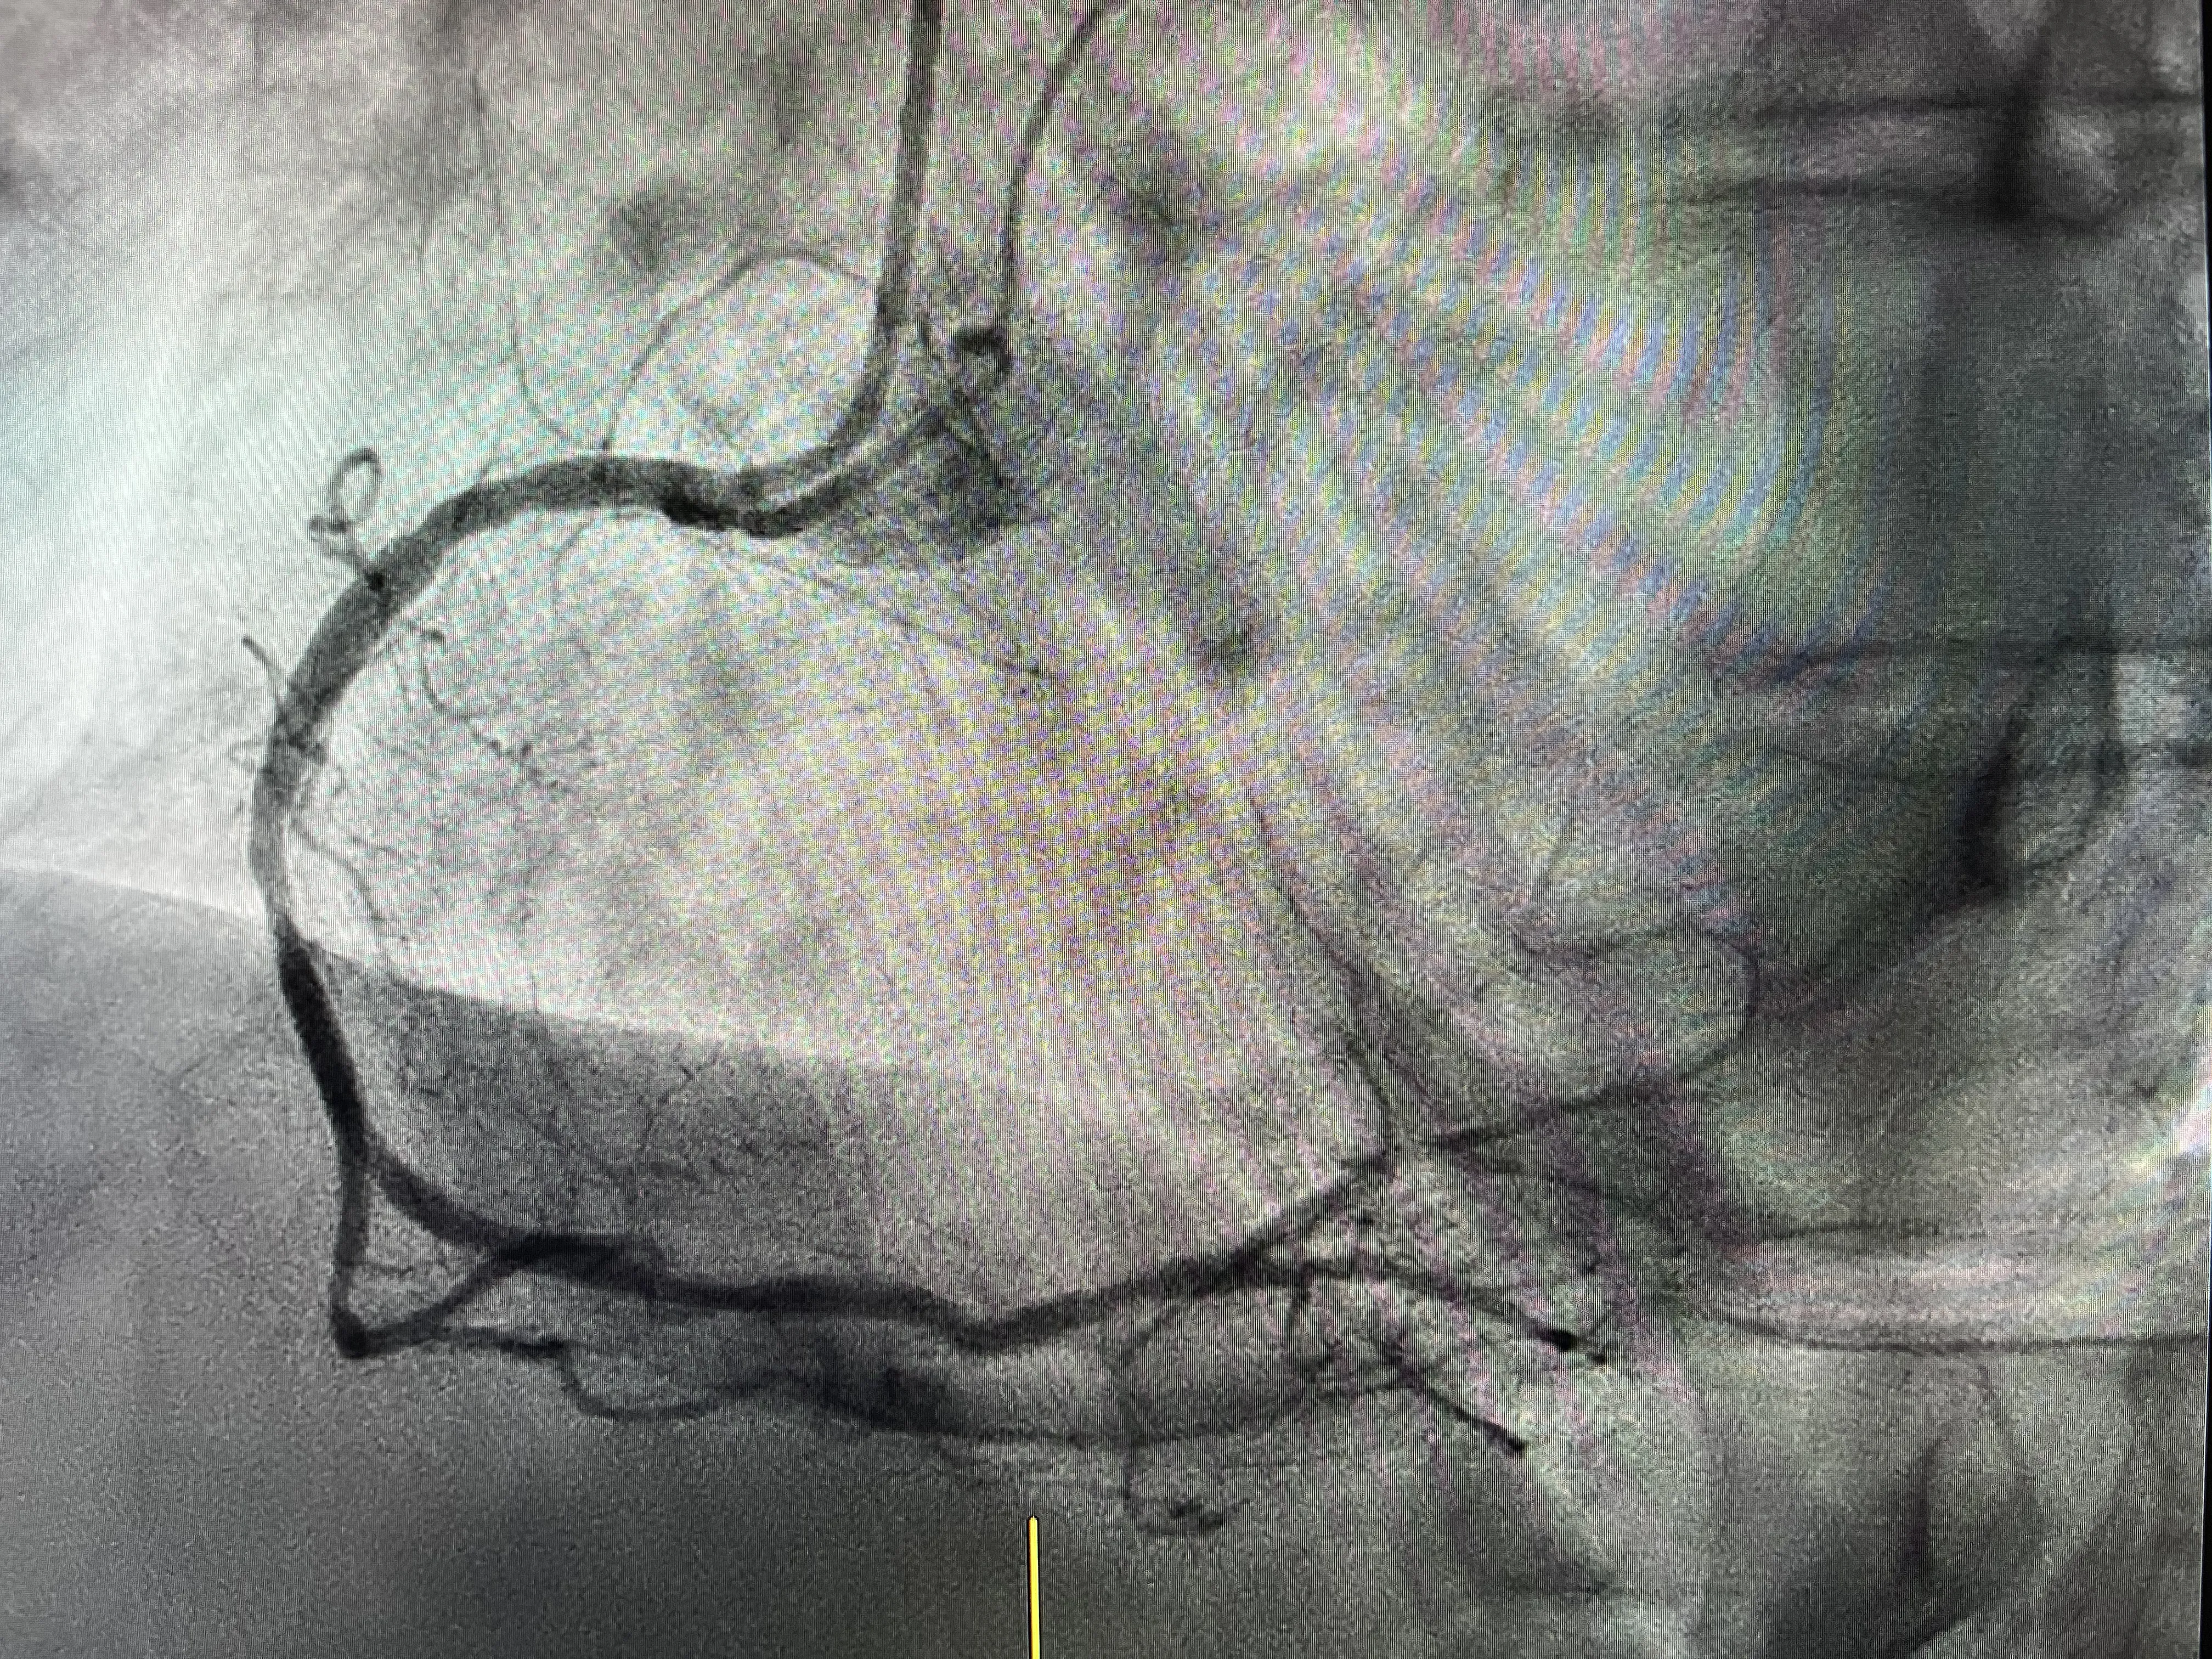

Lesión en la coronaria izquierda (DA) y dudas sobre severidad

En la coronaria izquierda, específicamente en la arteria descendente anterior (DA), se identificó una lesión que generó dudas sobre su severidad. La evaluación visual no siempre es suficiente para determinar el grado de obstrucción, por lo que se decidió utilizar una guía de presión para obtener una valoración más precisa. Esta herramienta es esencial para decidir si una lesión requiere intervención.

Predilatación de la lesión e implante del stent

Una vez confirmada la severidad de la lesión, se llevó a cabo la predilatación de la arteria afectada. Este procedimiento consiste en ensanchar temporalmente la arteria para facilitar la colocación del stent. El implante del stent se realizó sin complicaciones, asegurando que la arteria permaneciera abierta y permitiendo un flujo sanguíneo adecuado. Esta intervención fue crucial para prevenir un infarto y mejorar la calidad de vida del paciente.